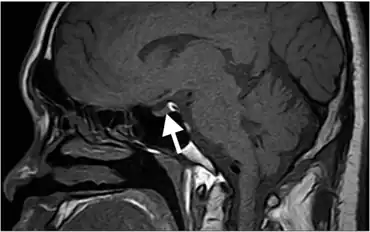

| Hyperintense signal of posterior pituitary on image could not be detected, lack of this bright spot is typical of central diabetes insipidus. | |